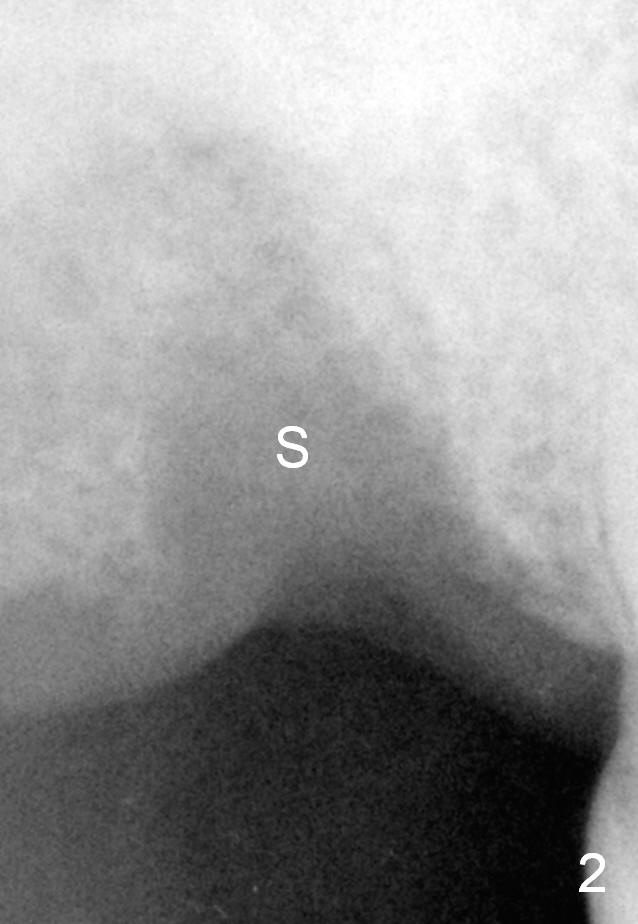

A 76-year-old man had the tooth #2 extracted (due to endo failure) 2 weeks ago (Fig.1). The socket looks "empty" (Fig.2 S, basis for osteotomes). It consists of the buccal (pink dashed line) and palatal (red) ones (Fig.3). In one word, the socket is pyramidal. It appears that a tapered implant is appropriate for the site. Clinically, the socket is healing with soft tissue covering the opening of the socket.